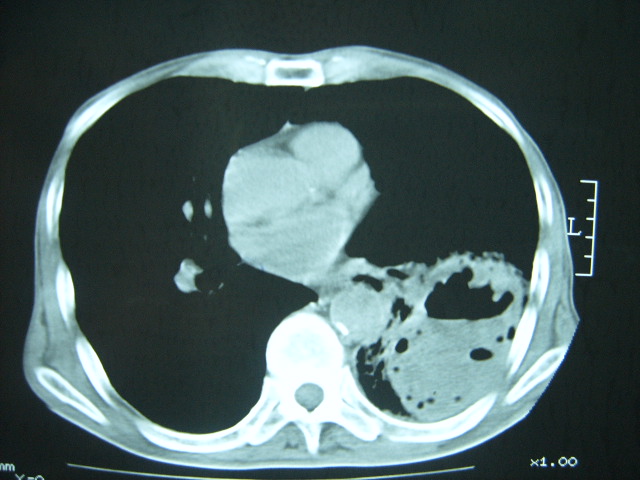

男74岁,咳嗽,寒战,低烧。有糖尿病史。

两肺结核,空洞形成,左下肺肺段隔离症待排

考虑:1、左下肺脓肿;

2、双肺结核。

考虑:糖尿病合并:1、左下肺炎继发肺脓肿;

考虑:1、左下肺脓肿;不排除霉菌感染

1、左下肺肺脓肿,合并霉菌球形成?.2、双肺陈旧性病灶.3、右上肺病灶警惕瘢痕癌,建议定期复查.

两肺结核,左下肺大片实变,内见空洞性病变,壁不规则,结合糖尿病史,考虑:结核性?霉菌性?建议结合实验室检查或治疗后复查。